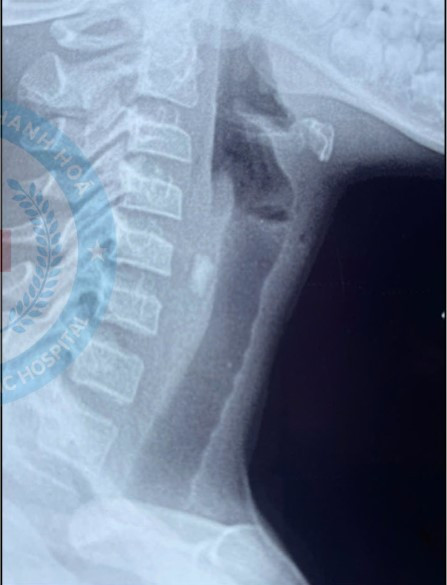

| Hình ảnh mảnh kính trên phim chụp - Ảnh BVCC |

Tại Bệnh viện Nhi Thanh Hóa trẻ được chụp CT Scan cổ tiêm thuốc cản quang với Hình ảnh mảnh kính găm vào vùng cổ trước bên trái, ngang mức đốt sống cổ C5, kích thước dị vật là 13*7mm, cách động mạch cảnh bên trái chỉ 2.5mm, cách mặt trước đốt sống 5mm, cách bờ thùy bên trái tuyến giáp 1mm, cách bờ trái thực quản 6mm.